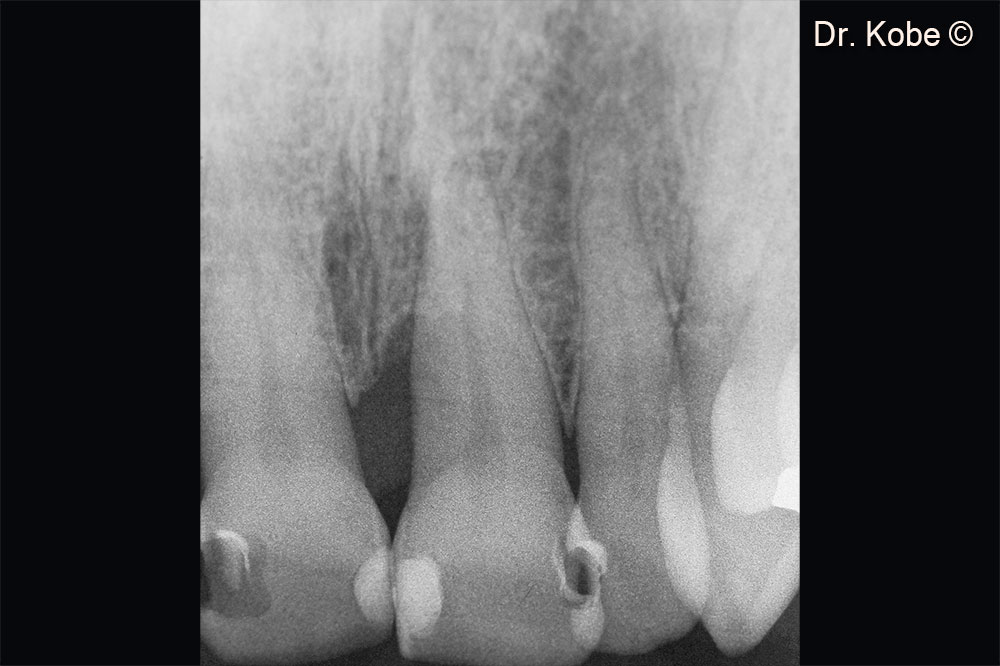

2. Vertical bone defect on the x-ray image

10. Initial x-ray